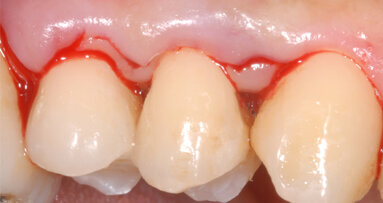

I follow-up devono essere considerati fondamentali per mantenere condizioni di salute, o rendere reversibile una condizione di gengivite (Van der Weijden, 2005) attraverso la terapia parodontale non chirurgica o una efficace gestione della terapia di supporto per il mantenimento domiciliare di cure implantari. È la seduta di igiene orale professionale una condizione urgente e di emergenza necessaria per la salute del cavo orale? Le evidenze scientifiche lo confermano. In questo momento di Pandemia i pazienti hanno prestato particolare attenzione allo stile di vita di igiene orale domiciliare? Forse non è stata attenzionata abbastanza attraverso la comunicazione quanto può essere necessario mantenere livelli di efficace controllo sull’igiene orale domiciliare.

Ma come risolvere il controllo degli stili di vita domiciliari? È opportuno scegliere kit domiciliari che permettano aderence ai protocolli domiciliari ed efficacia nel controllo del biofilm batterico manuale attraverso lo spazzolamento di superfici dento parodontali e degli spazi interprossimali ed efficacia del controllo chimico con uso di dentifrici/gel/collutori. Differenti evidenze scientifiche hanno dimostrato una maggiore sopravvivenza implantare se i pazienti seguono una terapia di supporto con particolare attenzione al controllo dell’efficacia della terapia domiciliare (Lang et al., 1994; Lang e Berglundh, 2011; Nyman e Lindhe, 2003; 2008). Altra criticità sono i pazienti affetti da gengiviti non indotte da placca, dai pazienti che sono costretti a terapie farmacologiche che provocano aumenti gengivali che hanno bisogno di un monitoraggio continuo.

Ed è per questo che l’approccio DOHMA Digital Oral Hygiene Motivation Approach (G.M. Nardi et al.) attraverso teleconsulti che permettono in remoto, grazie alla partecipazione attiva dei pazienti, di valutare in remoto, con utilizzo di specchio, fotografie e l’ascolto su quanto visualizzato e percepito dagli stessi, la condizione clinica presente. La condivisione di eventuali mutamenti dei tessuti dento-parodontali, il controllo di eventuale infiammazione presente con l’attenzione a visualizzare il colore del tessuto gengivale, il controllo delle mucose e della lingua, il rilevamento di pigmentazioni o white spots sulle superfici dentali, la presenza di ipersensibilità e il controllo attraverso lo sniff test dell’alito, può portare il professionista a valutare quale modifiche vanno apportate negli stili di vita di igiene orale, nella dieta alimentare e personalizzare gli strumenti opportuni per un’efficace igiene domiciliare.